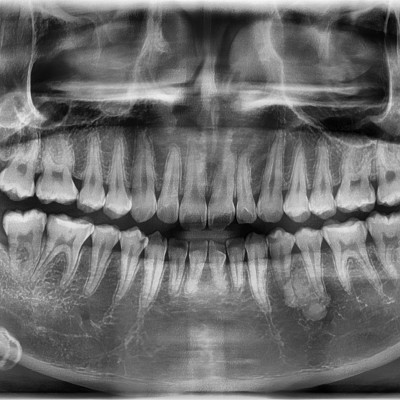

#18,28,48 사랑니 발치 #18,28,48 사랑니 발치 구강 외과 전문의가 당일 발치했습니다. ---------------------..

작성자 이턱이 작성일 02-11 조회 48